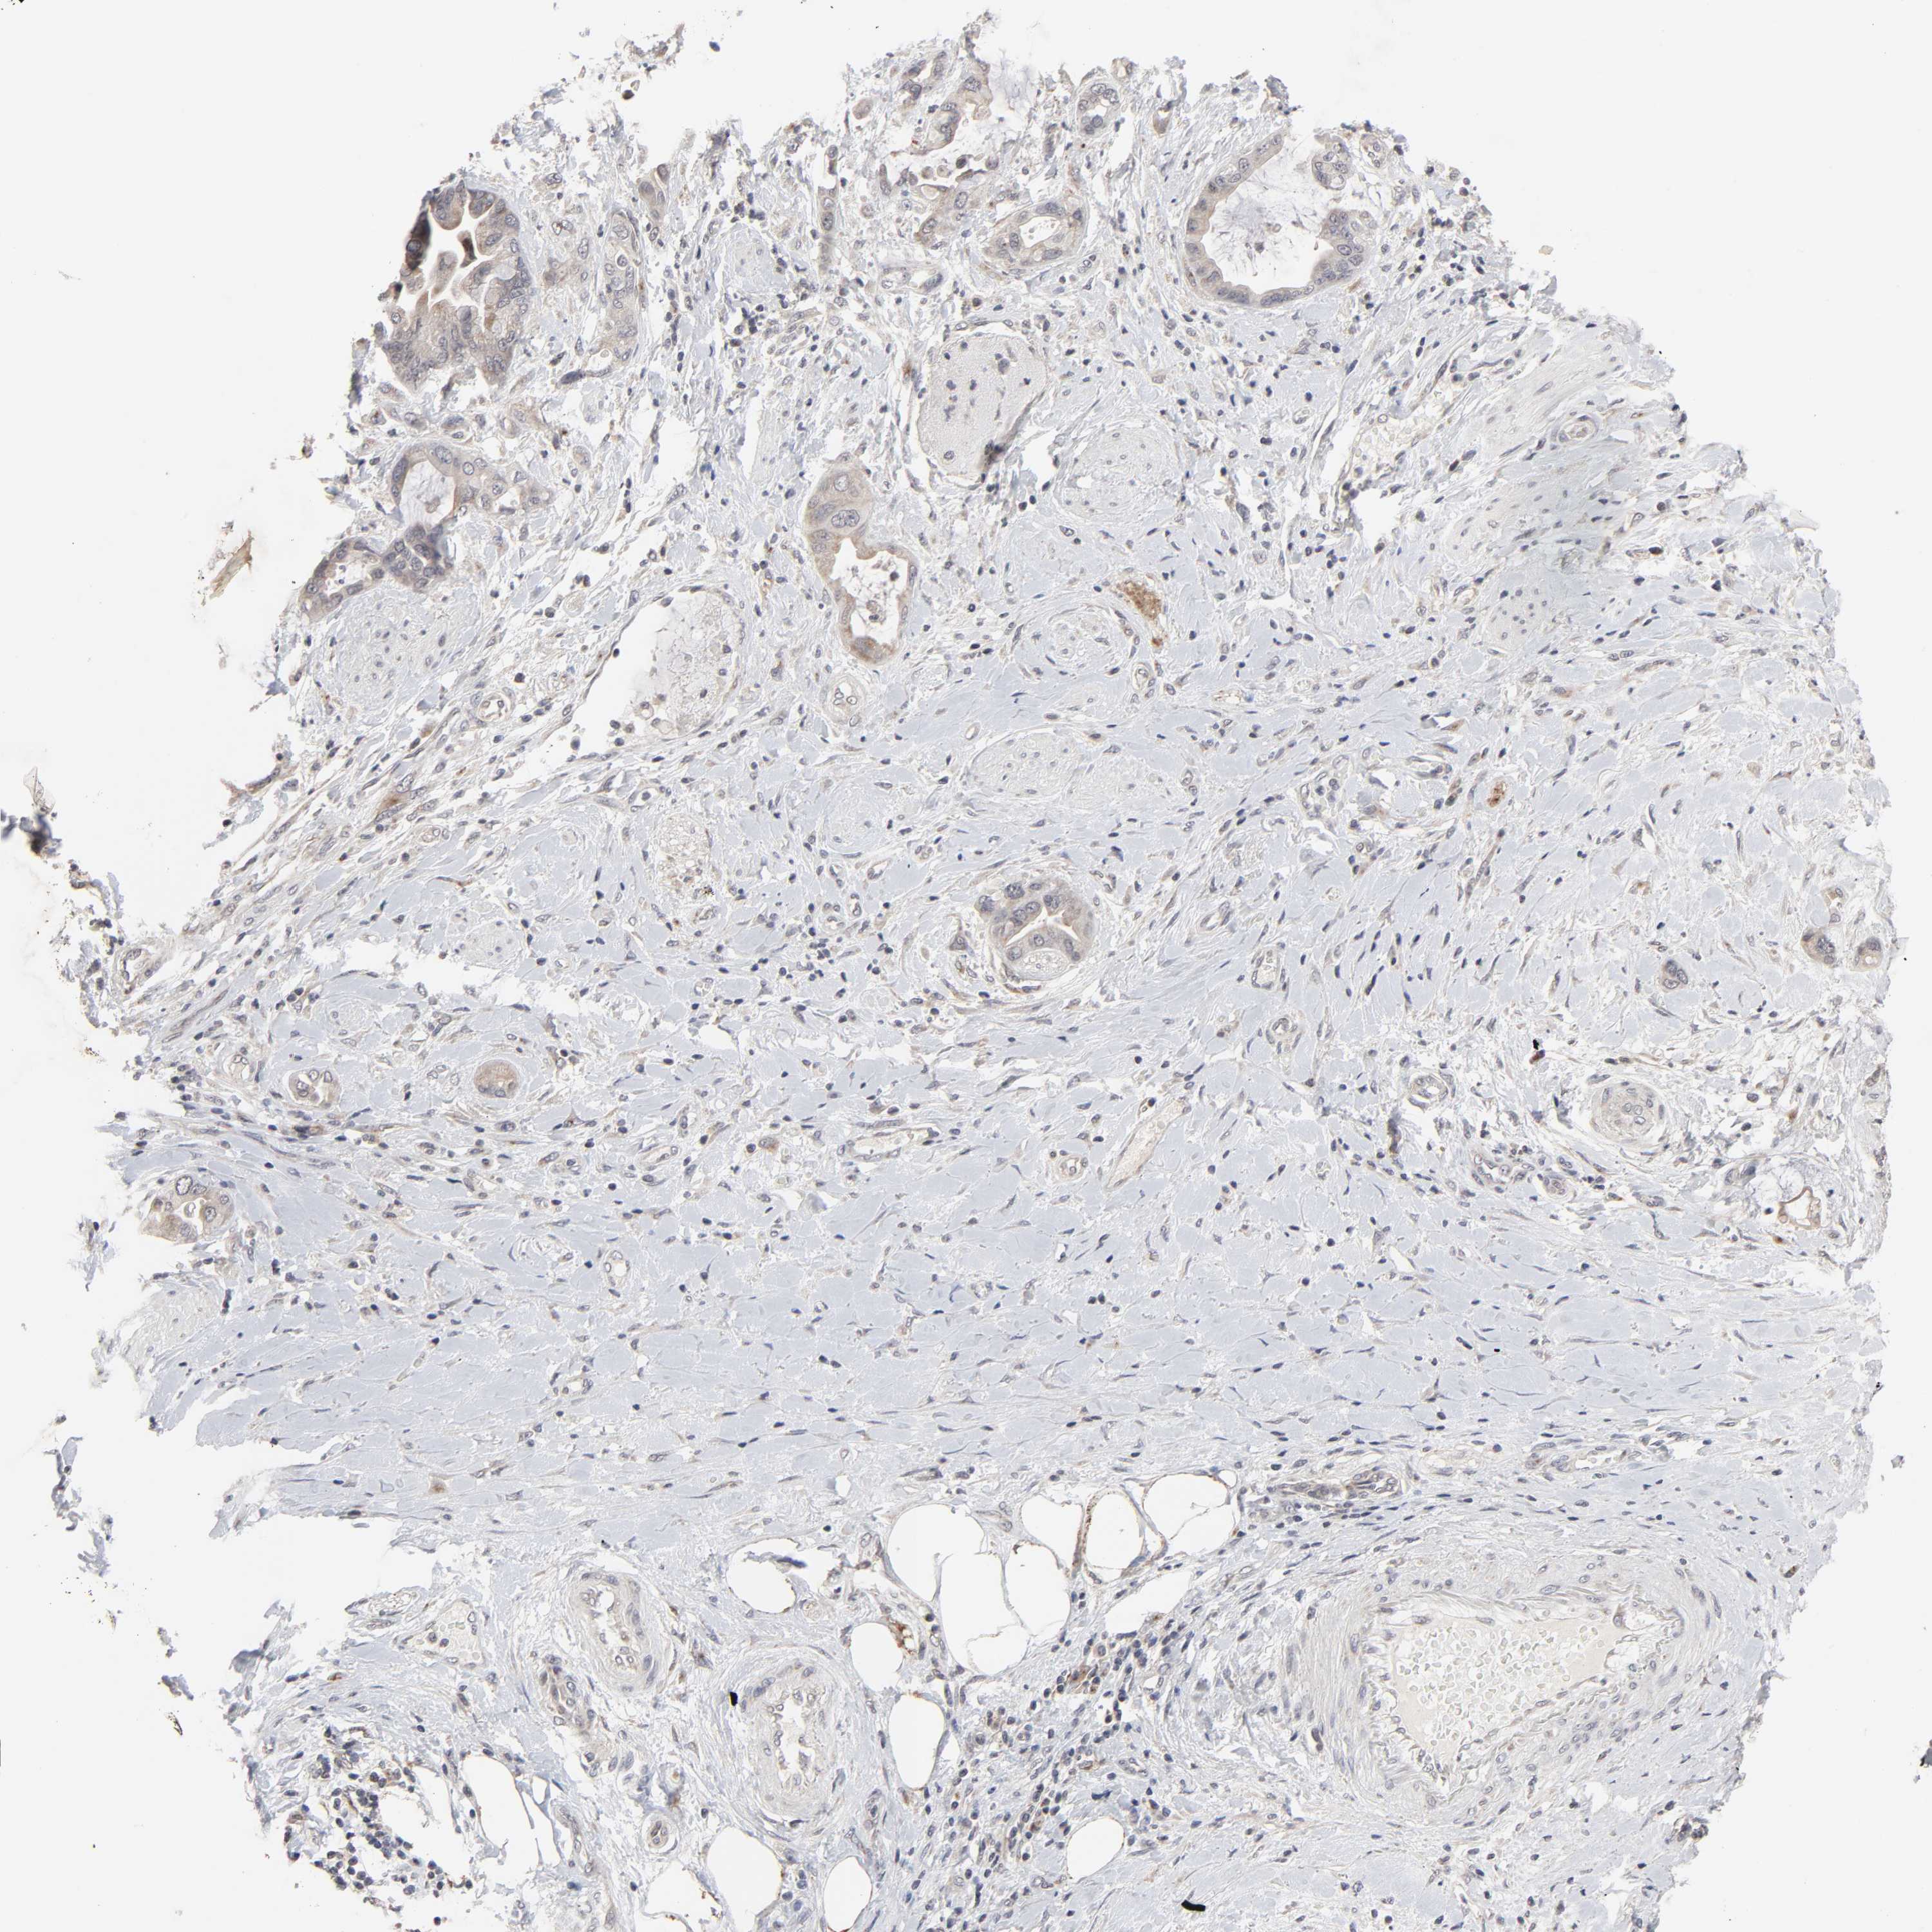

PANCREATIC CANCER - Protein expressioni

A mouse-over function shows sample information and annotation data. Click on an image to view it in a full screen mode. Samples can be filtered based on level of antibody staining by selecting one or several of the following categories: high, medium, low and not detected. The assay and annotation is described here.

Note that samples used for immunohistochemistry by the Human Protein Atlas do not correspond to samples in the TCGA dataset.

Antibody stainingi

Antibody staining in the annotated cell types in the current human tissue is reported as not detected, low, medium, or high, based on conventional immunohistochemistry profiling in selected tissues. This score is based on the combination of the staining intensity and fraction of stained cells.

Each image is clickable and will lead to virtual microscopy that enables deeper exploration of all samples and also displays staining intensity scores, fraction scores and subcellular localization as well as patient and tissue information for each sample.

Antibody HPA004171

Staining

High

Medium

Low

Not detected

Intensity

Strong

Moderate

Weak

Negative

Quantity

>75%

75%-25%

<25%

None

Location

Nuclear

Cytoplasmic/membranous

Cytoplasmic/membranous,nuclear

Adenocarcinoma, NOS

Adenocarcinoma, metastatic, NOS